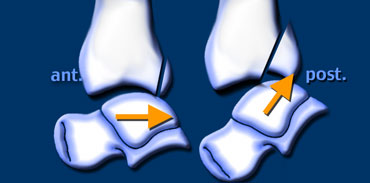

Isolated Tertius fracture

A fracture of the posterior malleolus as an isolated finding is very uncommon.

It is seen when someone's foot hits the ground and a fragment of the posterior malleolus is pushed off by the talus.

The size of this fragment depends on the direction of the force (figure).